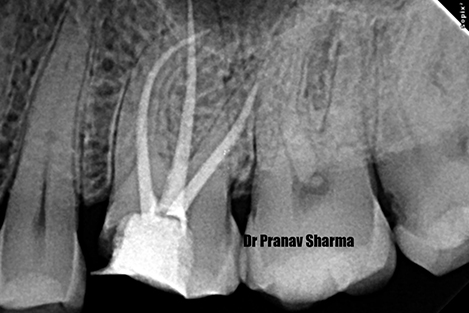

Post n Core